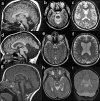

X-linked disorders with cerebellar dysgenesis (XLCD) are a genetically heterogeneous and clinically variable group of disorders in which the hallmark is a cerebellar defect (hypoplasia, atrophy or dysplasia) visible on brain imaging, caused by gene mutations or genomic imbalances on the X-chromosome. The neurological features of XLCD include hypotonia, developmental delay, intellectual disability, ataxia and/or other cerebellar signs. Normal cognitive development has also been reported. Cerebellar dysgenesis may be isolated or associated with other brain malformations or multiorgan involvement. There are at least 15 genes on the X-chromosome that have been constantly or occasionally associated with a pathological cerebellar phenotype. 8 XLCD loci have been mapped and several families with X-linked inheritance have been reported. Recently, two recurrent duplication syndromes in Xq28 have been associated with cerebellar hypoplasia. Given the report of several forms of XLCD and the excess of males with ataxia, this group of conditions is probably underestimated and families of patients with neuroradiological and clinical evidence of a cerebellar disorder should be counseled for high risk of X-linked inheritance.